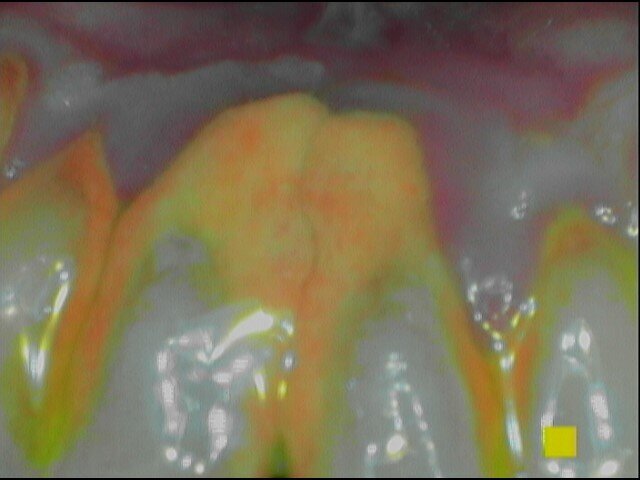

Vengono rilevati gli indici clinici e vengono condivise con il paziente le immagini raccolte con la videocamera intraorale, così da motivarlo di fronte alla presenza di tartaro e infiammazione gengivale e mostrargli le aree critiche. Viene apposto il rilevatore di placca alla fluorescina ed illuminato da una lampada fotopolimeralizzante, che permette di visualizzare la topografia del biofilm batterico (D-BIOTEK-TECNICHE)2, in modo da condividere con il paziente i siti più a rischio del cavo orale (Figg. 1a-2f).